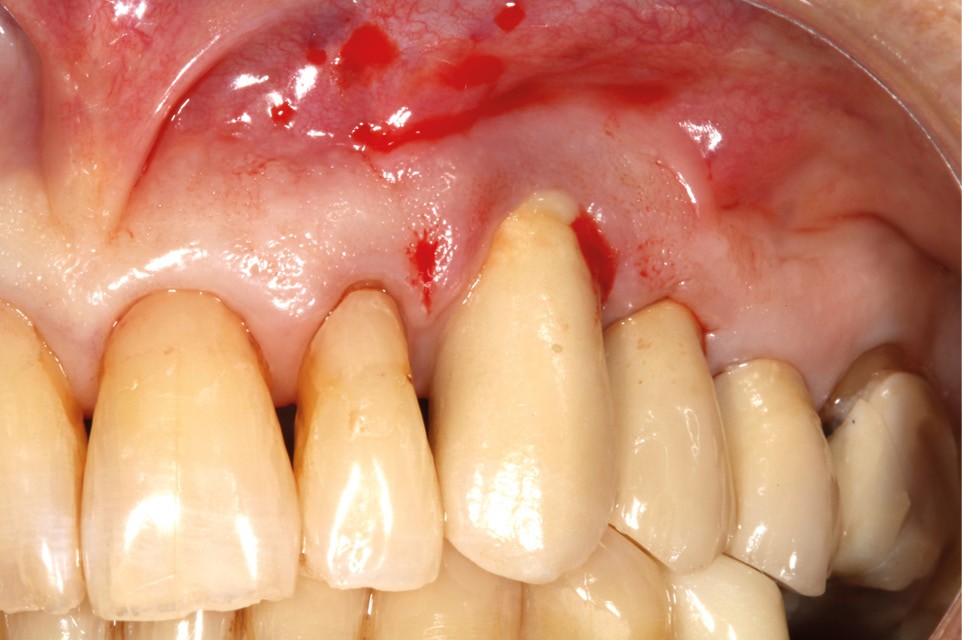

Le patient

- 70 ans

- Pas d’antécédents médicaux

- Ne fume pas

- Hygiène correcte

L’implant

- Site 23

- Mis en place il y a 12 ans